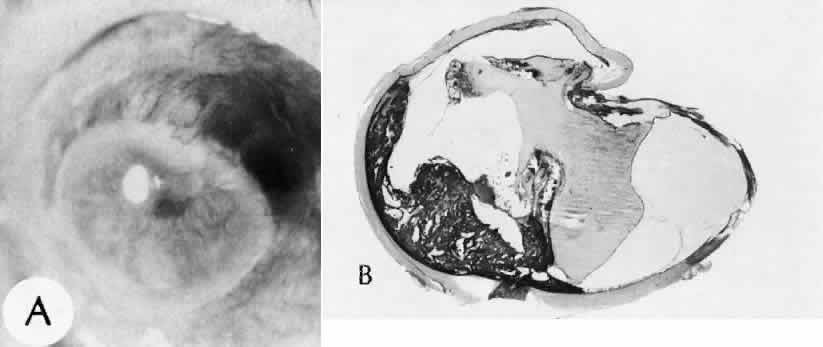

Fig. 24. An unusual complication of cataract surgery. A. An unsuspected uveal mass was noted in the region of the pupil following cataract extraction. The mass was determined to be a metastatic carcinoma. The globe was enucleated. B. In a section of the enucleated globe, extensive tumor (T) can be identified though one hemisphere of the choroid, causing a secondary retinal detachment (RD). The detached retina is herniated through the cataract wound. (Hematoxylin-eosin stain; × 5.)

Expulsive choroidal hemorrhage (Fig. 30) is a rare catastrophic complication often resulting in total loss of the eye.93 The site of hemorrhage is probably a sclerotic choroidal arteriole where the vessel crosses the suprachoroidal space from the scleral canal. The sudden hypotension after surgical penetration of the globe causes a bending and then a rupture of the arteriole.94 Although most hemorrhages are massive and immediate, they occasionally are delayed, and some may not occur for days or weeks after surgery. Delayed choroidal hemorrhage may occur at the time of corneoscleral suture removal,95 because of clinically unapparent wound dehiscence or as a result of perforation of a corneal ulcer.

Fig. 30. A case of expulsive choroidal hemorrhage. A. Expulsive choroidal hemorrhage occurred 3 weeks after cataract surgery at the time when a limbal suture was removed. The intraocular pressure was reduced enough to allow shearing forces in the superficial choroid to tear an arteriole resulting in a high-pressure hemorrhage. B. In another case enucleated shortly after cataract extraction because of expulsive hemorrhage, accumulated blood can be identified in the suprachoroidal space. Because of the loose attachment of the choroid to the sclera, all intraocular contents were displaced toward the cataract wound. (Hematoxylin-eosin stain; × 3.)

Histologically, massive choroidal hemorrhagic detachment is associated with a retinal detachment. The retina and choroid may herniate through the scleral wound. A ruptured ciliary artery may be found in the suprachoroidal space.